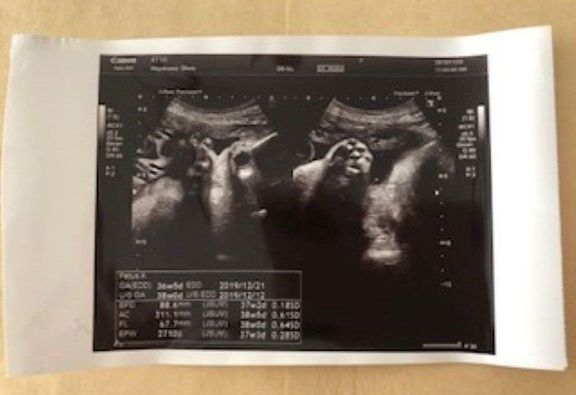

36w5d 2710g -